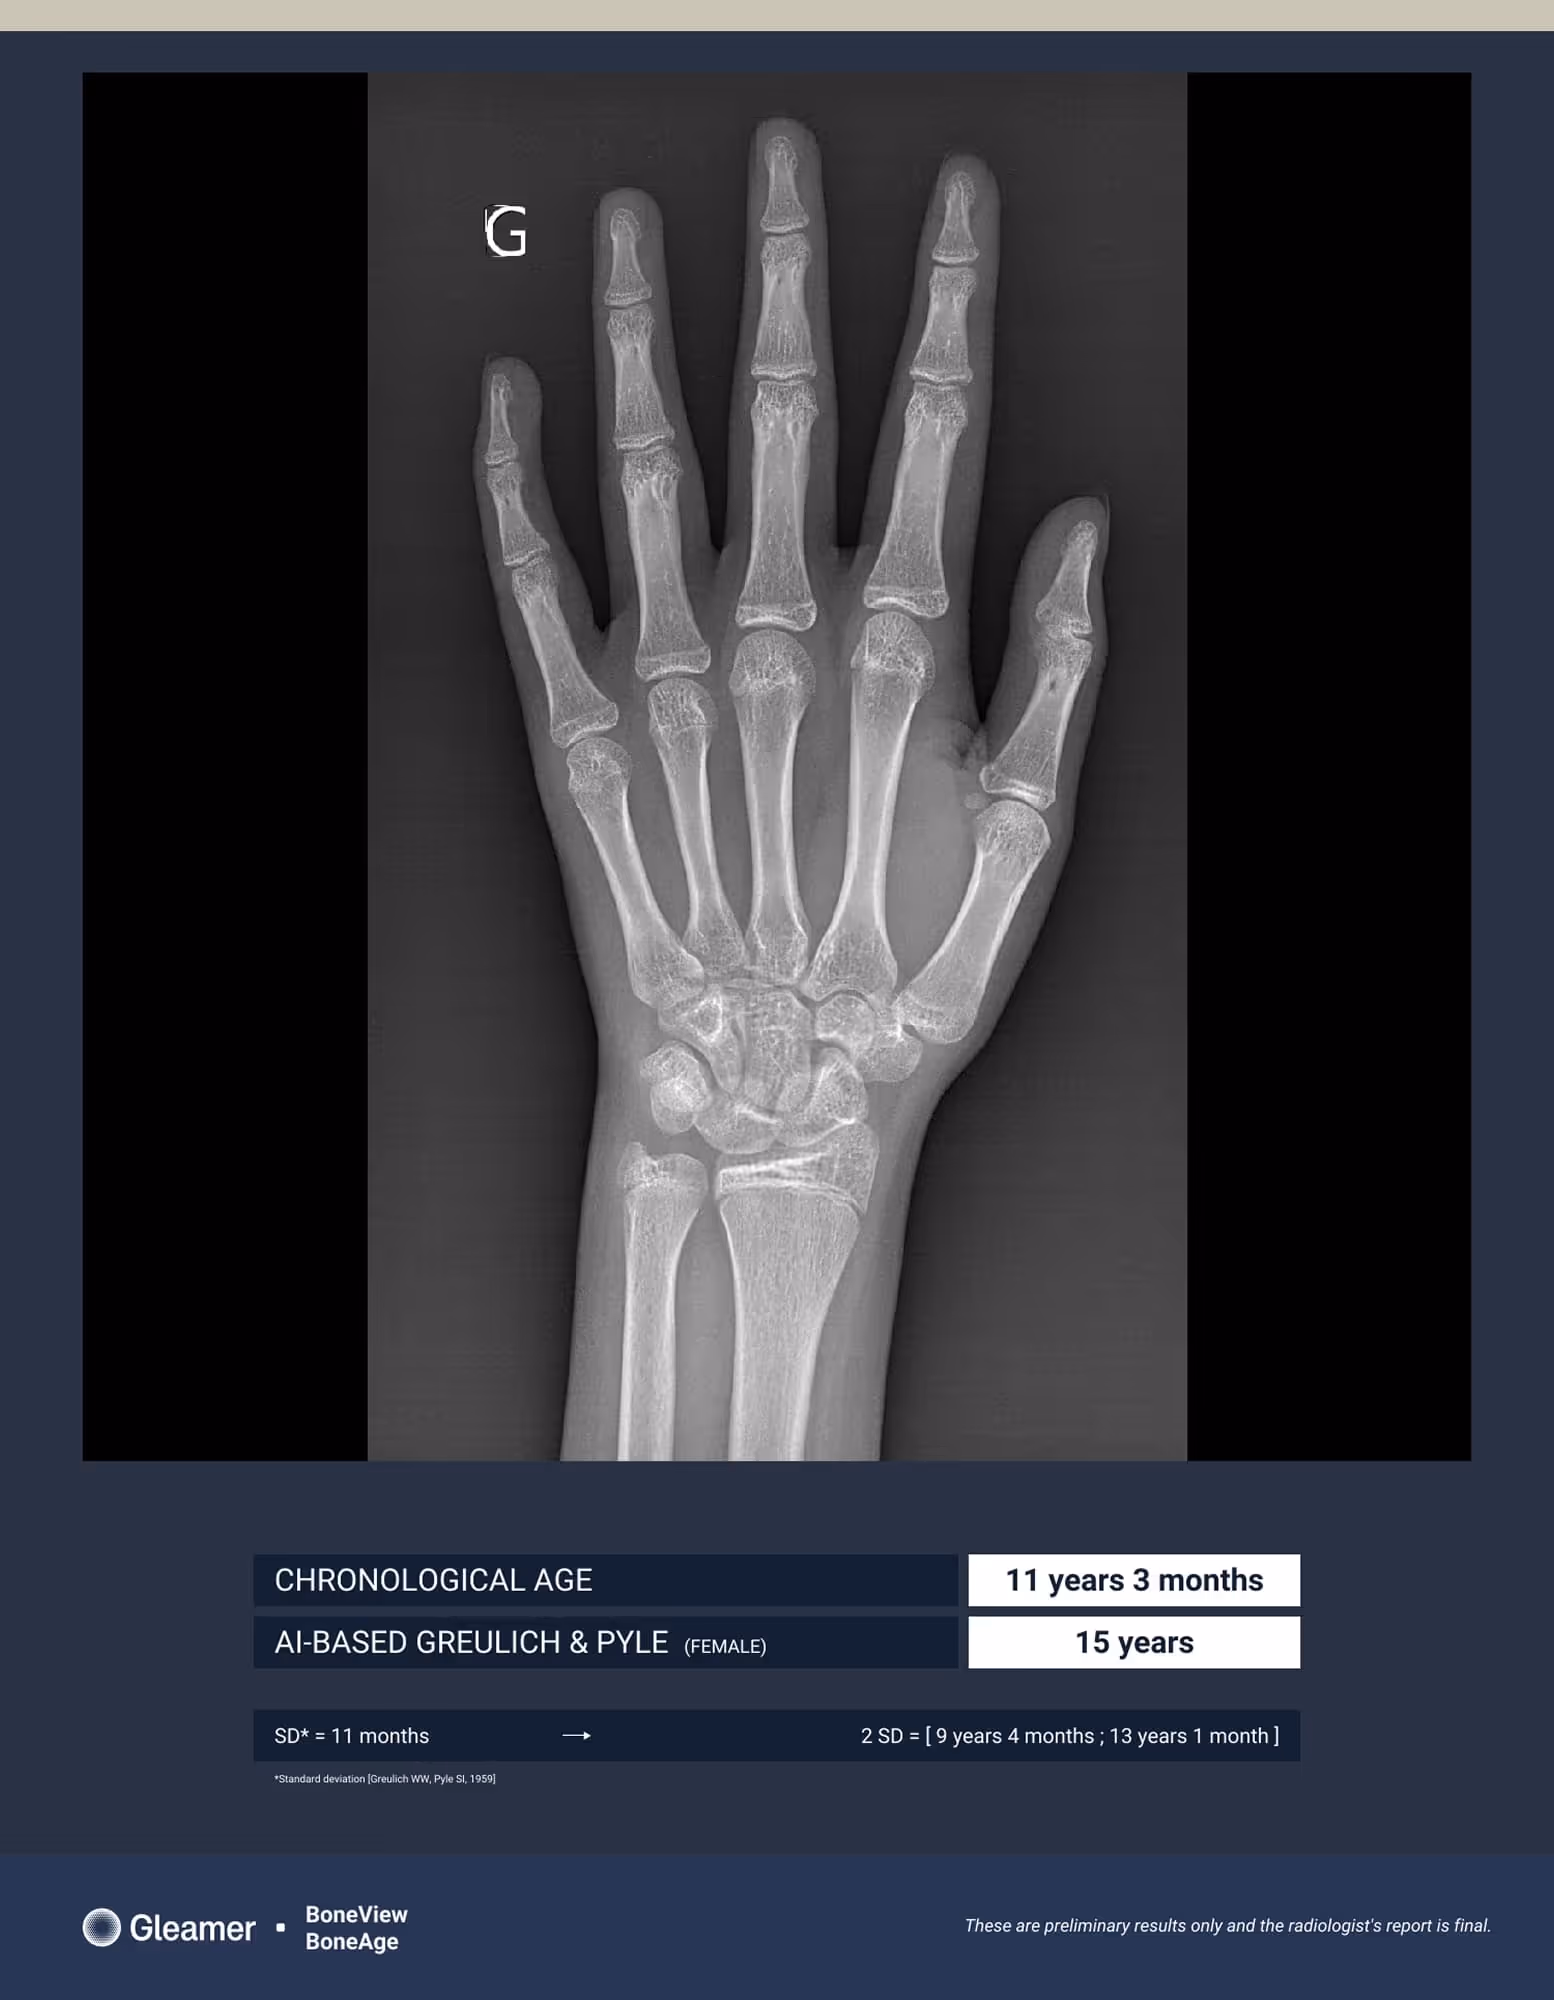

An 11-year-old girl presenting for bone age assessment due to signs of early puberty.

BoneAge analysis indicates an advanced bone age compared to the patient’s chronological age.

BoneAge is designed for frontal hand acquisition using the Greulich & Pyle method.